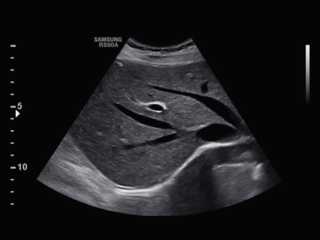

Athena Medica - Centro Diagnostico offre un ambiente professionalmente e tecnologicamente avanzato in continuo aggiornamento, particolarmente attento a garantire qualità e attendibilità dei risultati. Ultimamente il Centro, si è dotato di un nuovo Ecografo, il SAMSUNG RS80A, di ultimissima generazione, con lo scopo di offrire una sempre maggiore qualità ed efficienza diagnostica.

Si tratta di uno strumento dalle prestazioni eccellenti: touch screen da 10,1″ per una migliore usabilità e monitor LED da 18,5″ per una ottimizzazione delle immagini cliniche. Questo Ecofrafo innovativo consente diagnosi rapide e offre maggiore sicurezza durante il trattamento, maggiore precisione diagnostica e un’esperienza migliore per il paziente. Le attività diagnostiche sono garantite dall’utilizzo di tecnologie all’avanguardia e top di gamma, con un’ottima qualità dell’immagine e a bassa esposizione dei pazienti a raggi ionizzanti.

Questa rivoluzionaria tecnologia offre risultati ottimizzati in una varietà di esami ecografici che possono spaziare dall'addome agli organi superficiali come tiroide, collo, parotidi, linfonodi, testicoli e pene, dall'Ecografia muscolo-tendinea a quella transrettale, per poi passare a quella endovaginale, ginecologica, mammaria sino a quella neonatale.